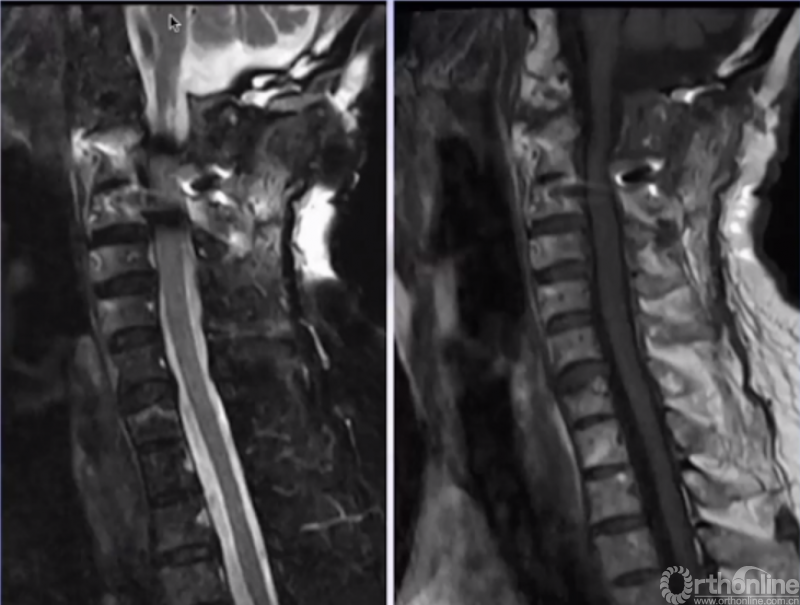

术后MRI(患者术后四肢麻木、乏力,发音、吞咽困难改善。)

患者术后未使用无创呼吸机,呼吸功能明显改善,术后3天血气分析恢复至正常范围